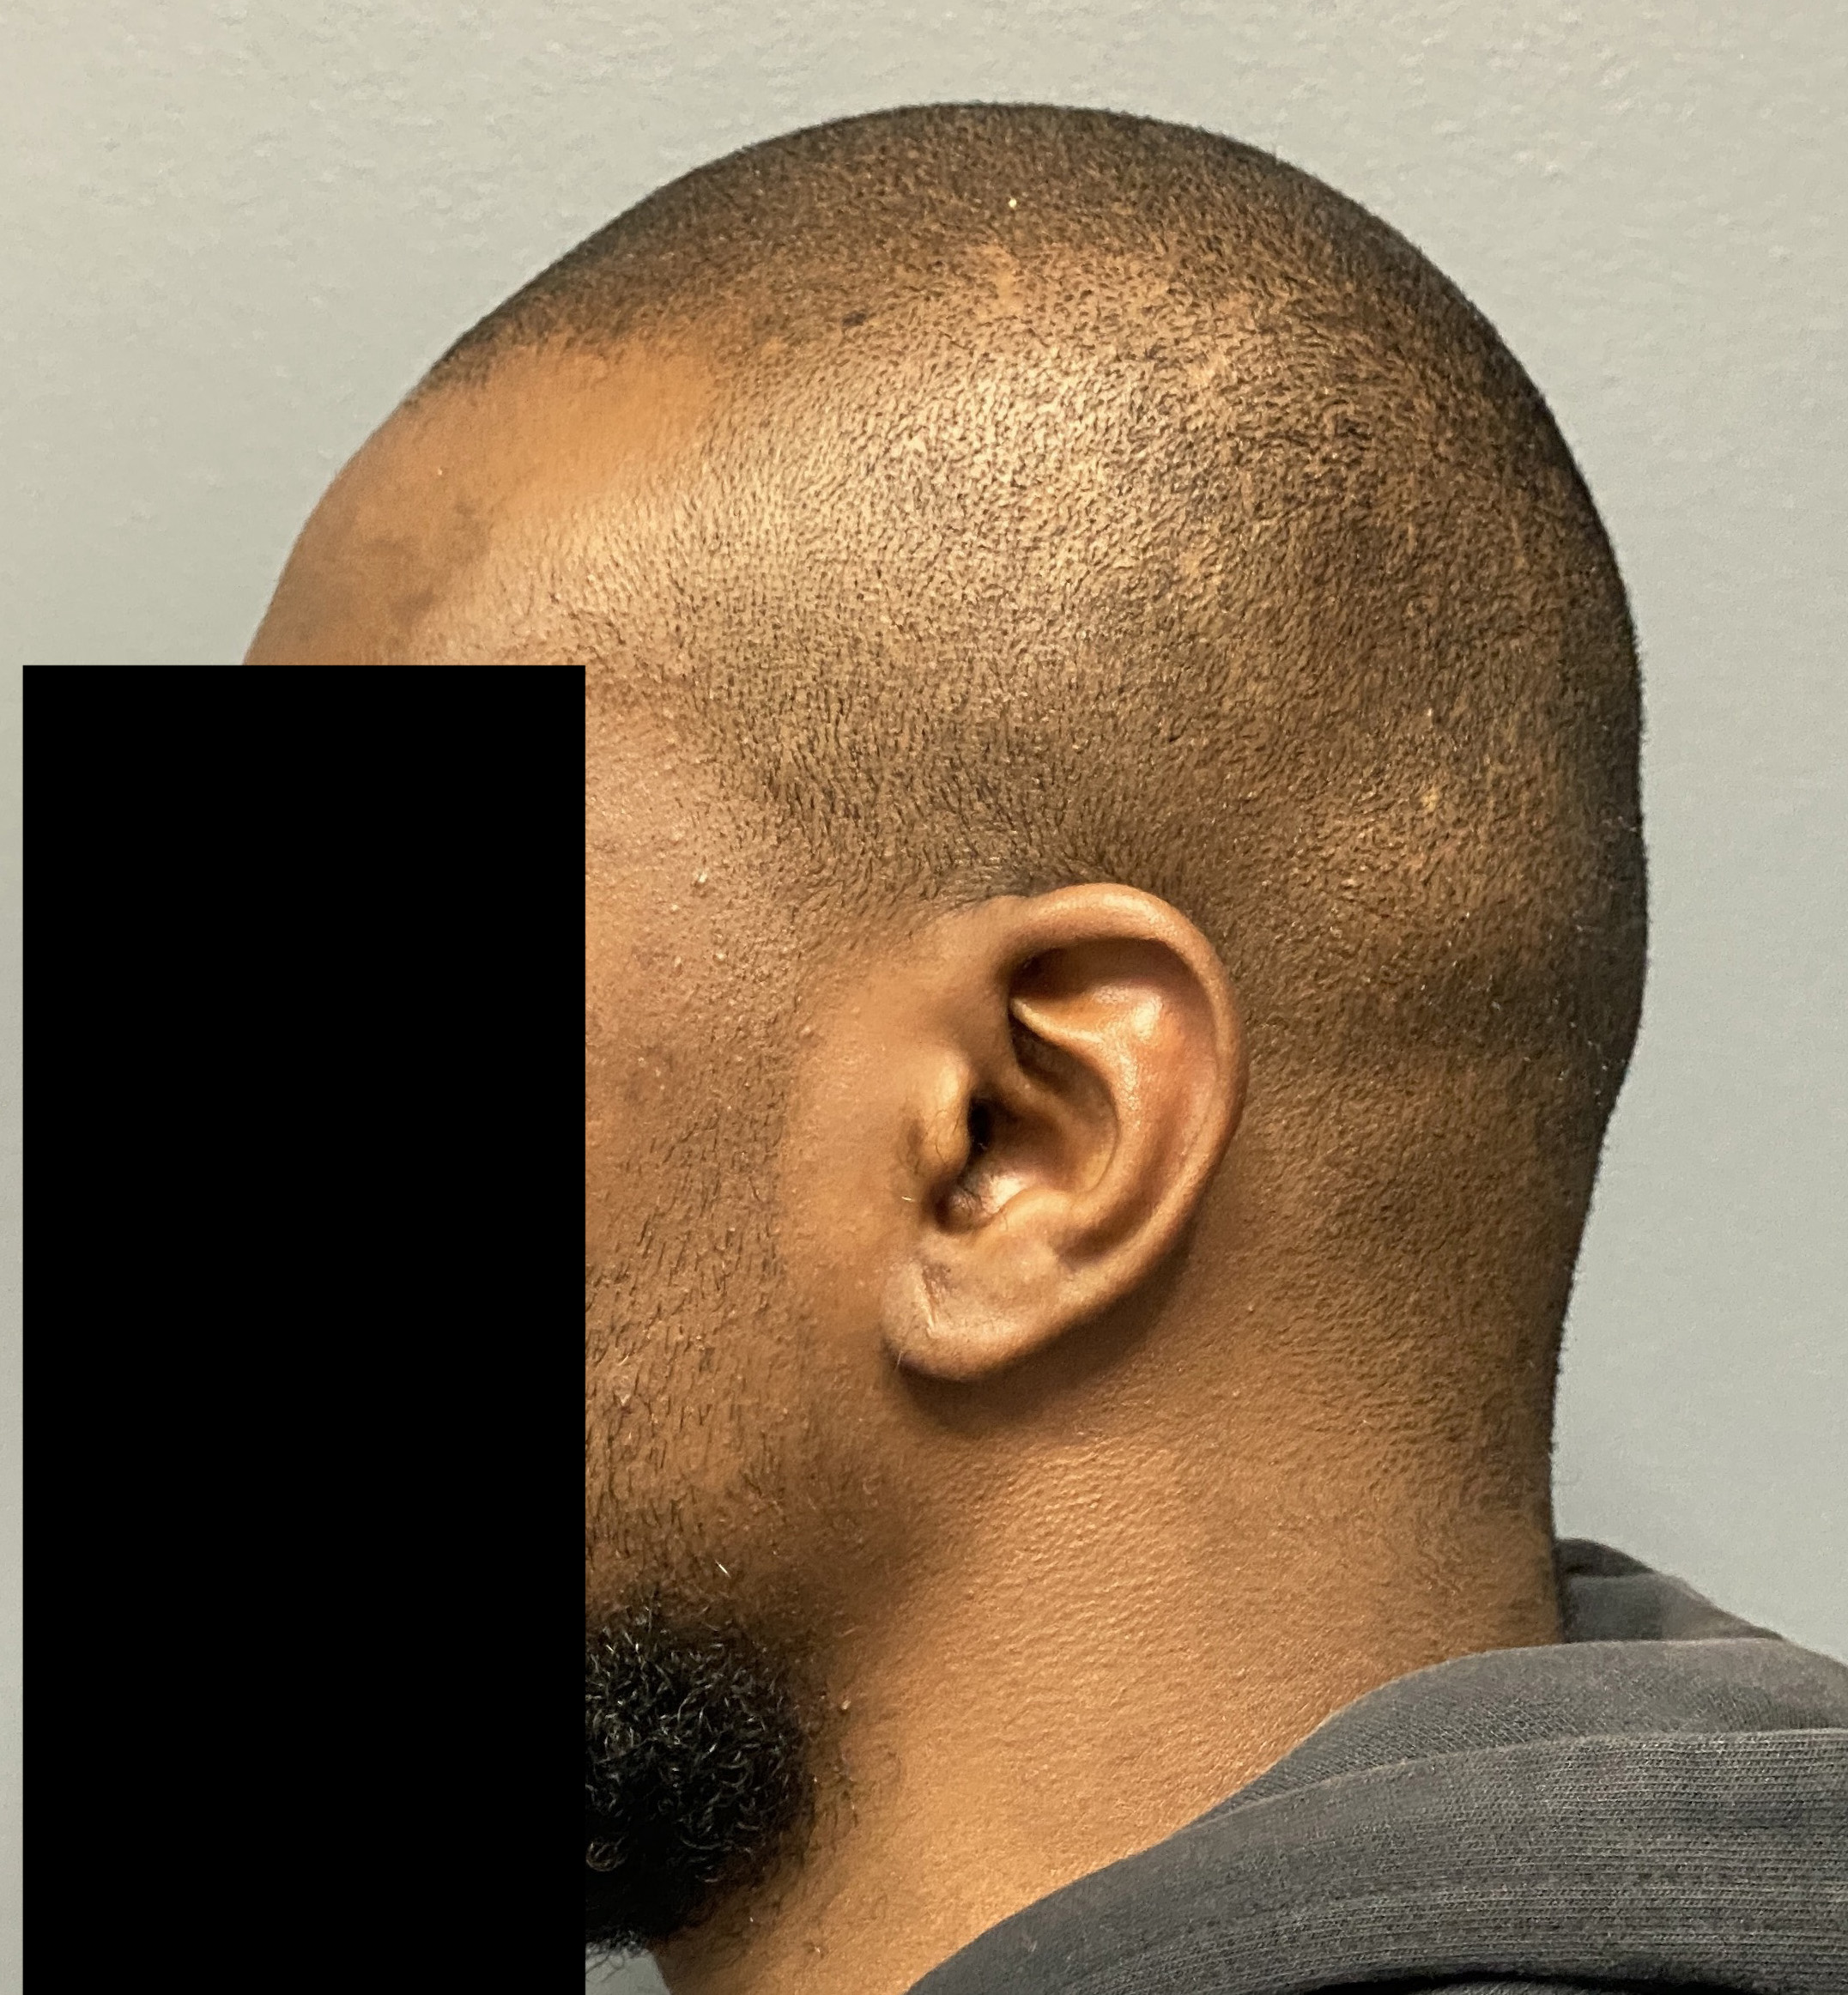

Patient 100

Desire for reshaping of an asymmetric flat back of the head in a shaved head male.

A combined back of the head reshaping procedure was done with a custom skull implant, sagittal ridge reduction and a right temporal muscle reduction.

Desire for reshaping of an asymmetric flat back of the head in a shaved head male.

A combined back of the head reshaping procedure was done with a custom skull implant, sagittal ridge reduction and a right temporal muscle reduction.